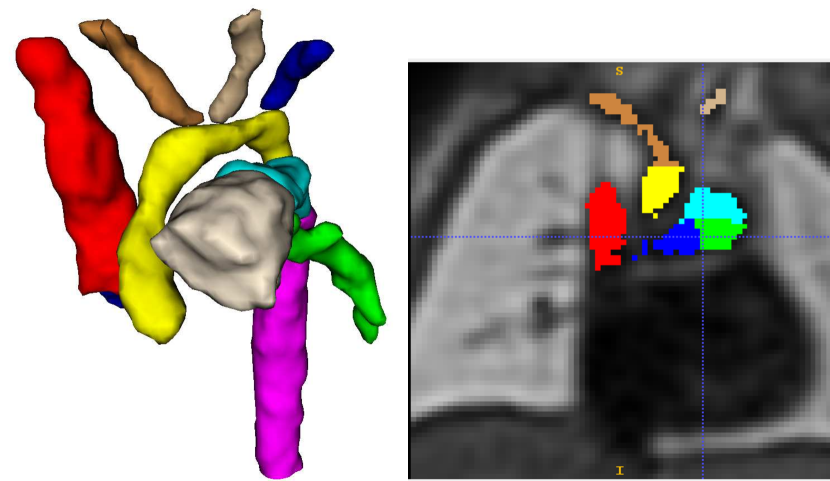

Trained clinicians manually segmented a binary vessels label for the majority of our subjects (N=181), Fig. 3(a). We employ propagated atlas labels exclusively for the remaining unsegmented cases (N=14, Sec. 2.2). In order to achieve our multi-class output, we employ three fully-labelled atlases111https://gin.g-node.org/SVRTK/ (Uus et al. (2022b), see Fig. 3(b)), one per anomaly (RAA, DAA and CoA). These include 11 manually segmented vascular regions for RAA and DAA, and 10 for CoA cases.

Our training dataset consists of partially labelled subjects (binary manually segmented labels) and fully-labelled atlases (Fig. 1). This type of setup is not uncommon in the medical imaging field, with exhaustive works addressing this challenge (Peng and Wang, 2021).

Our automated segmentation tool is aimed at subjects with Right Aortic Arch (RAA) with aberrant left subclavian artery (ALSA), Double Aortic Arch (DAA), and suspected Coarctation of the Aorta (CoA). These three distinct anomalies are depicted in Fig. 2.